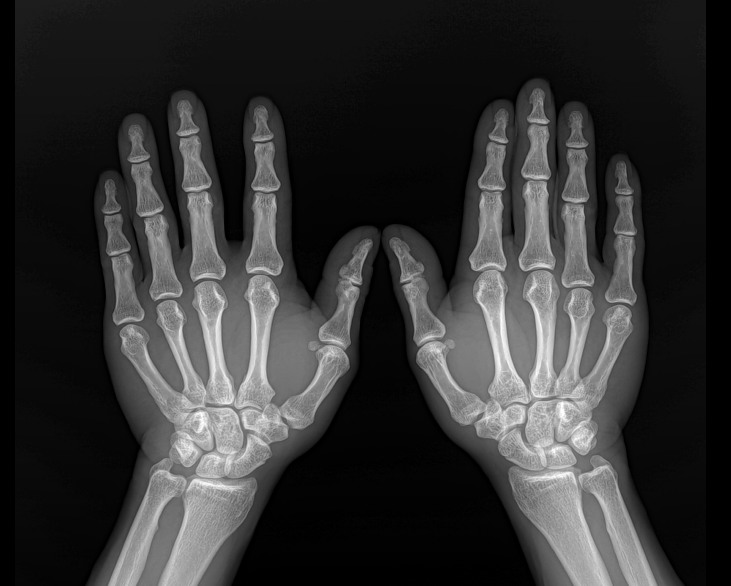

• Clinical Images